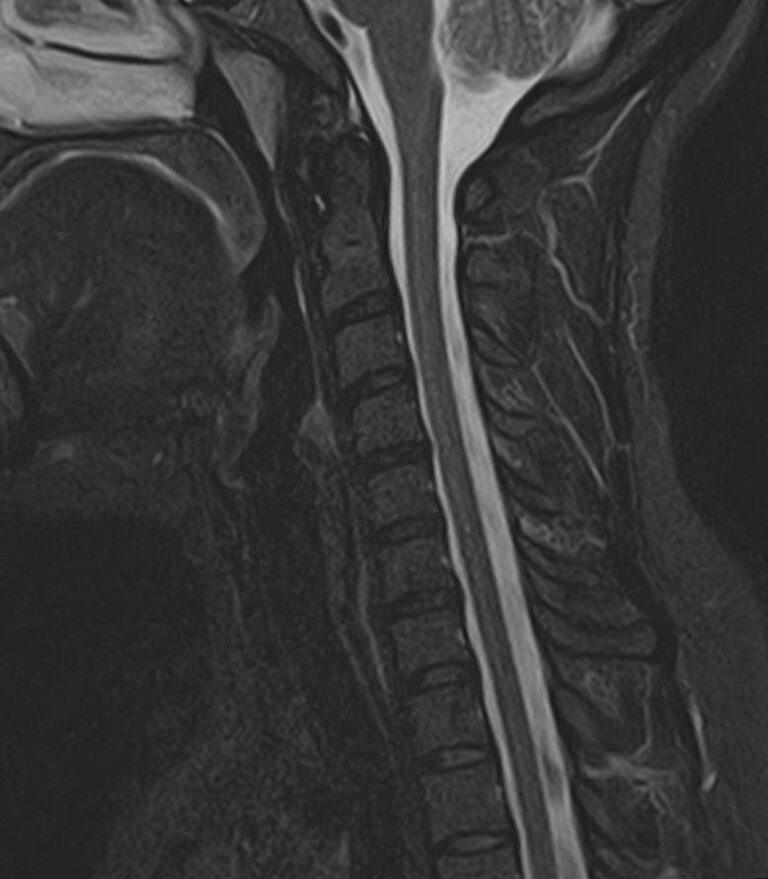

Шейный отдел позвоночника — это самый подвижный сегмент позвоночного столба, который испытывает повышенные нагрузки, подвержен травмам и развитию различных заболеваний. В эту анатомическую область входит 7 верхних позвонков, спинной мозг с отходящими от него нервными корешками, а также проходят крупные сосуды, кровоснабжающие головной мозг.

МРТ шейного отдела позвоночника позволяет проводить диагностику дегенеративных заболеваний позвоночного столба (в том числе межпозвонковых грыж, протрузий, остеохондроза), выявлять воспалительные, травматические изменения и объемные образования в области шейных позвонков и спинного мозга.

В клинике «Доступная медицина» данное исследование проводится на современном высокопольном магнитно-резонансном томографе экспертного класса TOSHIBA VANTAGE TITAN 1,5 Тесла. Напряженность магнитного поля 1,5 Тесла обеспечивает высокую разрешающую способность аппарата, что позволяет выявлять минимальные изменения в тканях и диагностировать заболевания на начальной стадии.

МРТ шейного отдела позвоночника позволяет выявить практически любые изменения в костных и мягких тканях. Исследование характеризуется высокой результативностью при следующих нарушениях:

• остеохондроз шейного отдела позвоночника;

• грыжи межпозвоночных дисков;

• компрессия спинномозговых корешков и спинного мозга;